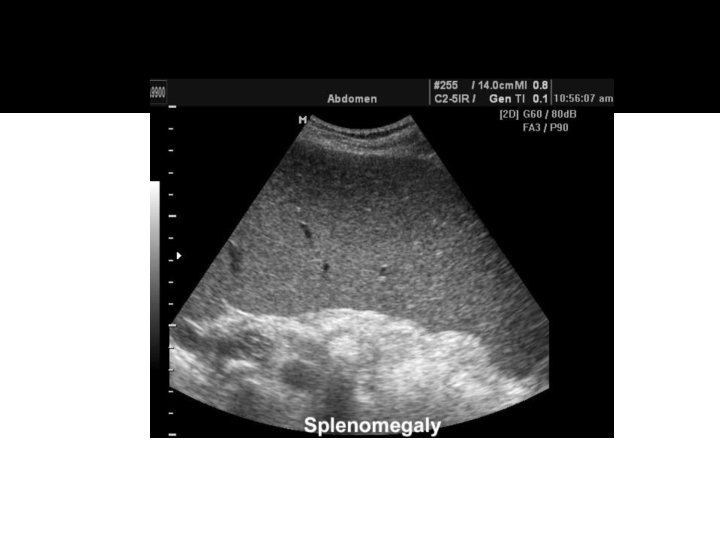

Splenomegaly �Splenomegaly is indicated with a longitudinal measurement > 12 cm or if the spleen is inferior to the lower pole of the left kidney.

Splenomegaly �Diffuse splenomegaly is the most common feature and manifestation of splenic disease. �The spleen may be enlarged in a variety of conditions including liver disease, blood disorders, infections, and neoplastic involvement. �With diffuse disease, the spleen may be less echogenic, more echoic, or have the same echogenicity as normal.

Splenomegaly